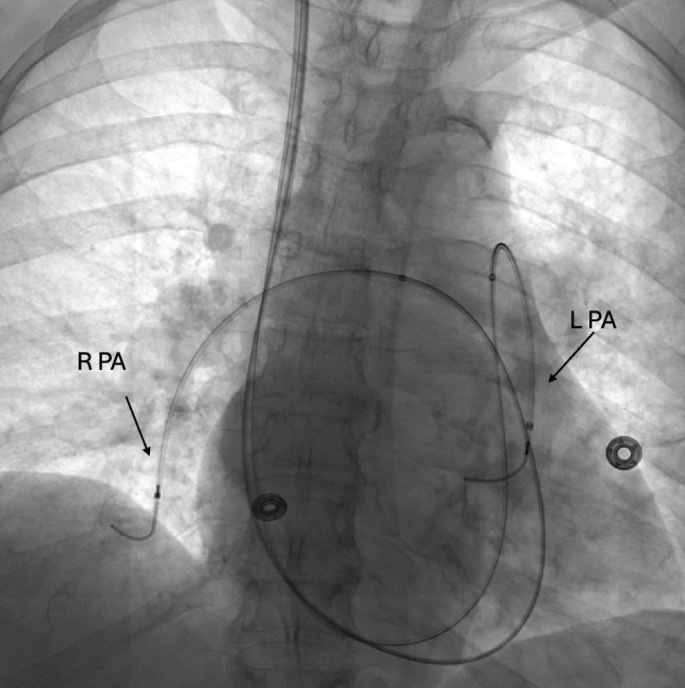

Therapeutic anticoagulation is the mainstay therapy in acute pulmonary embolism (PE), however, select patients benefit from emergent reperfusion to prevent or rescue acute right ventricular failure and haemodynamic collapse. Compared to other leading causes of cardiovascular mortality such as myocardial infarction and stroke, there is a substantial paucity of literature informing on advanced therapies in PE. Recent years have seen significant evolution in the armamentarium available for PE care with the uptake of several endovascular treatment modalities and increased use of mechanical circulatory support. While several ongoing randomised controlled trials may alter the therapeutic landscape and approach to PE management, at present, we are left with multiple selections with limited guidance. In this review, we discuss the latest therapeutic options available for acute PE and offer an approach to their implementation.